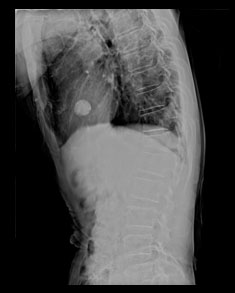

경피적 척추체 성형술 사진

| 수술전 |

수술후 |

압박골절로 인해서 추체가 압박되어 경도의 후만변형을 보이고 있는 상태이며, 수술 후 골절된 추체 내에 의료용 시멘트가 주입되어 있는 모습